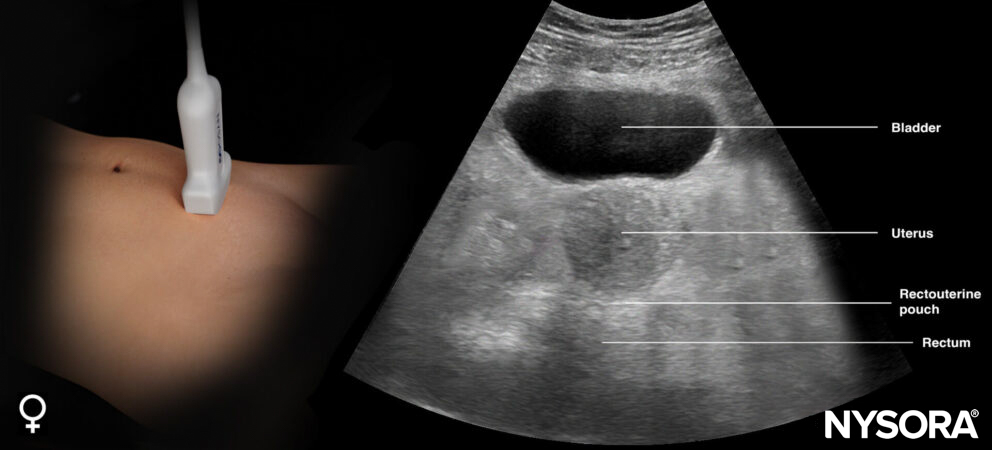

This view assesses the presence of free fluid in the pelvis.

- Position the transducer just above the pubic bone in the midline between the umbilicus and the pubic bone.

- The bladder can be used as an internal anatomical landmark to scan the area behind and lateral to the bladder for free fluid (rectovesical pouch in men and the rectouterine pouch or pouch of Douglas in women).

Sonoanatomy of interest in males:

Transducer position and ultrasound anatomy of the male pelvis.

Transducer position and reverse ultrasound anatomy of the male pelvis.

- Transverse view (orientation marker toward the patient’s right)

Sonoanatomy of interest in females:

Transducer position and ultrasound anatomy of the female pelvis.

Transducer position and reverse ultrasound anatomy of the female pelvis.